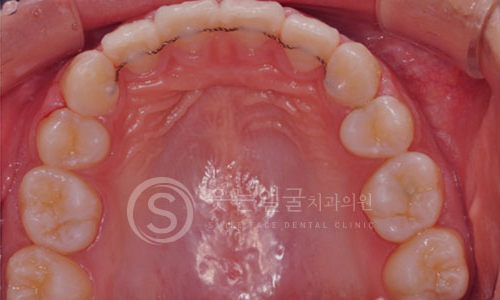

09 구내 촬영

한눈에 보는

치아교정 전후사진